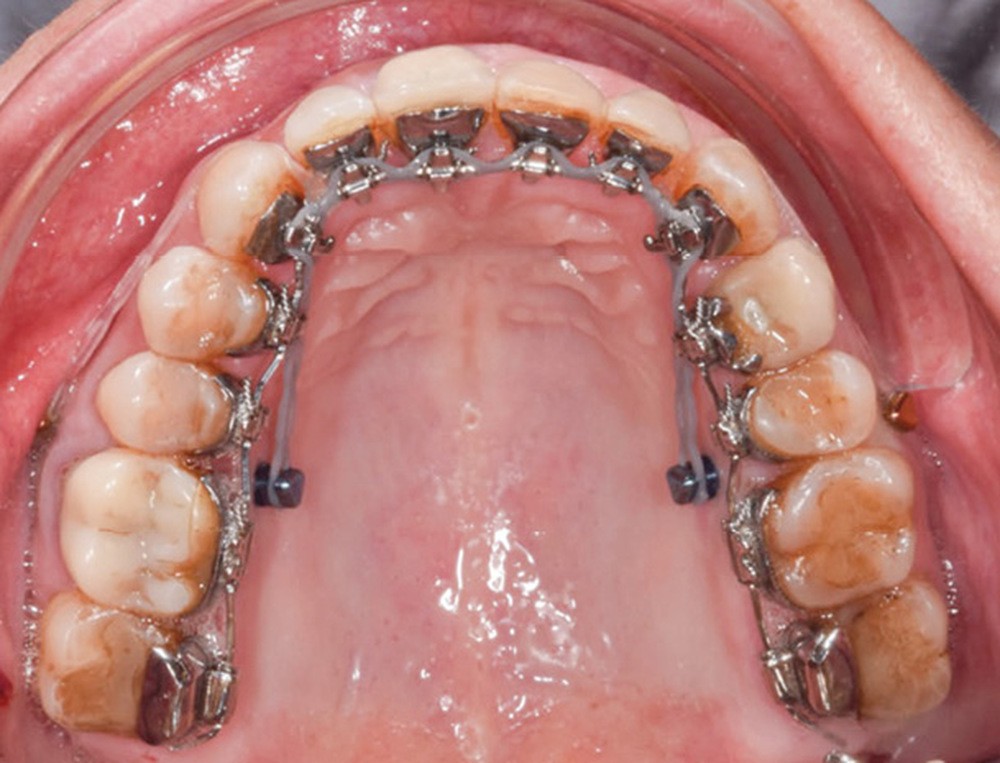

Séquences thérapeutiques (fig. 4)

La préparation de la denture consiste en un alignement et un nivellement. En orthodontie linguale totalement individualisée, le nivellement de la courbe de Spee est facilité par la présence des bases des attaches sur les incisives maxillaires qui provoquent une égression des secteurs postérieurs et une ingression et vestibulo-version des incisives mandibulaires. L’utilisation d’arcs acier ribbonwise .016 x .024 est également efficace pour ce nivellement [3].

La correction de la denture passe par la correction des torques incisifs grâce à des arcs acier maxillaires .016 x .024 extra torque 13° puis extra torque 21° qui permet le rétablissement d’un surplomb et par ce fait le déverrouillage mandibulaire.

La distalisation maxillaire par ancrages squelettiques temporaires peut alors commencer, 4 minivis sont mises en place pour une correction bilatérale : deux minivis sont placées en vestibulaire (8 mm) et deux minivis en palatin (10 mm) entre la seconde prémolaire et la première molaire maxillaire [4]. La distalisation peut ainsi avoir lieu progressivement, grâce à des chaînettes en double câble, vestibulaire et palatine.

Cette technique est associée à une mécanique de traction interarcade de classe II, l’action est surtout maxillaire puisqu’il y a présence d’un implant en 36. La traction élastomérique sera de 6 oz à droite et de 3,5 oz à gauche.

Les finitions et l’intercuspidation sont réalisées avec des arcs TMA .018 x .018 et avec des tractions interarcades verticales.